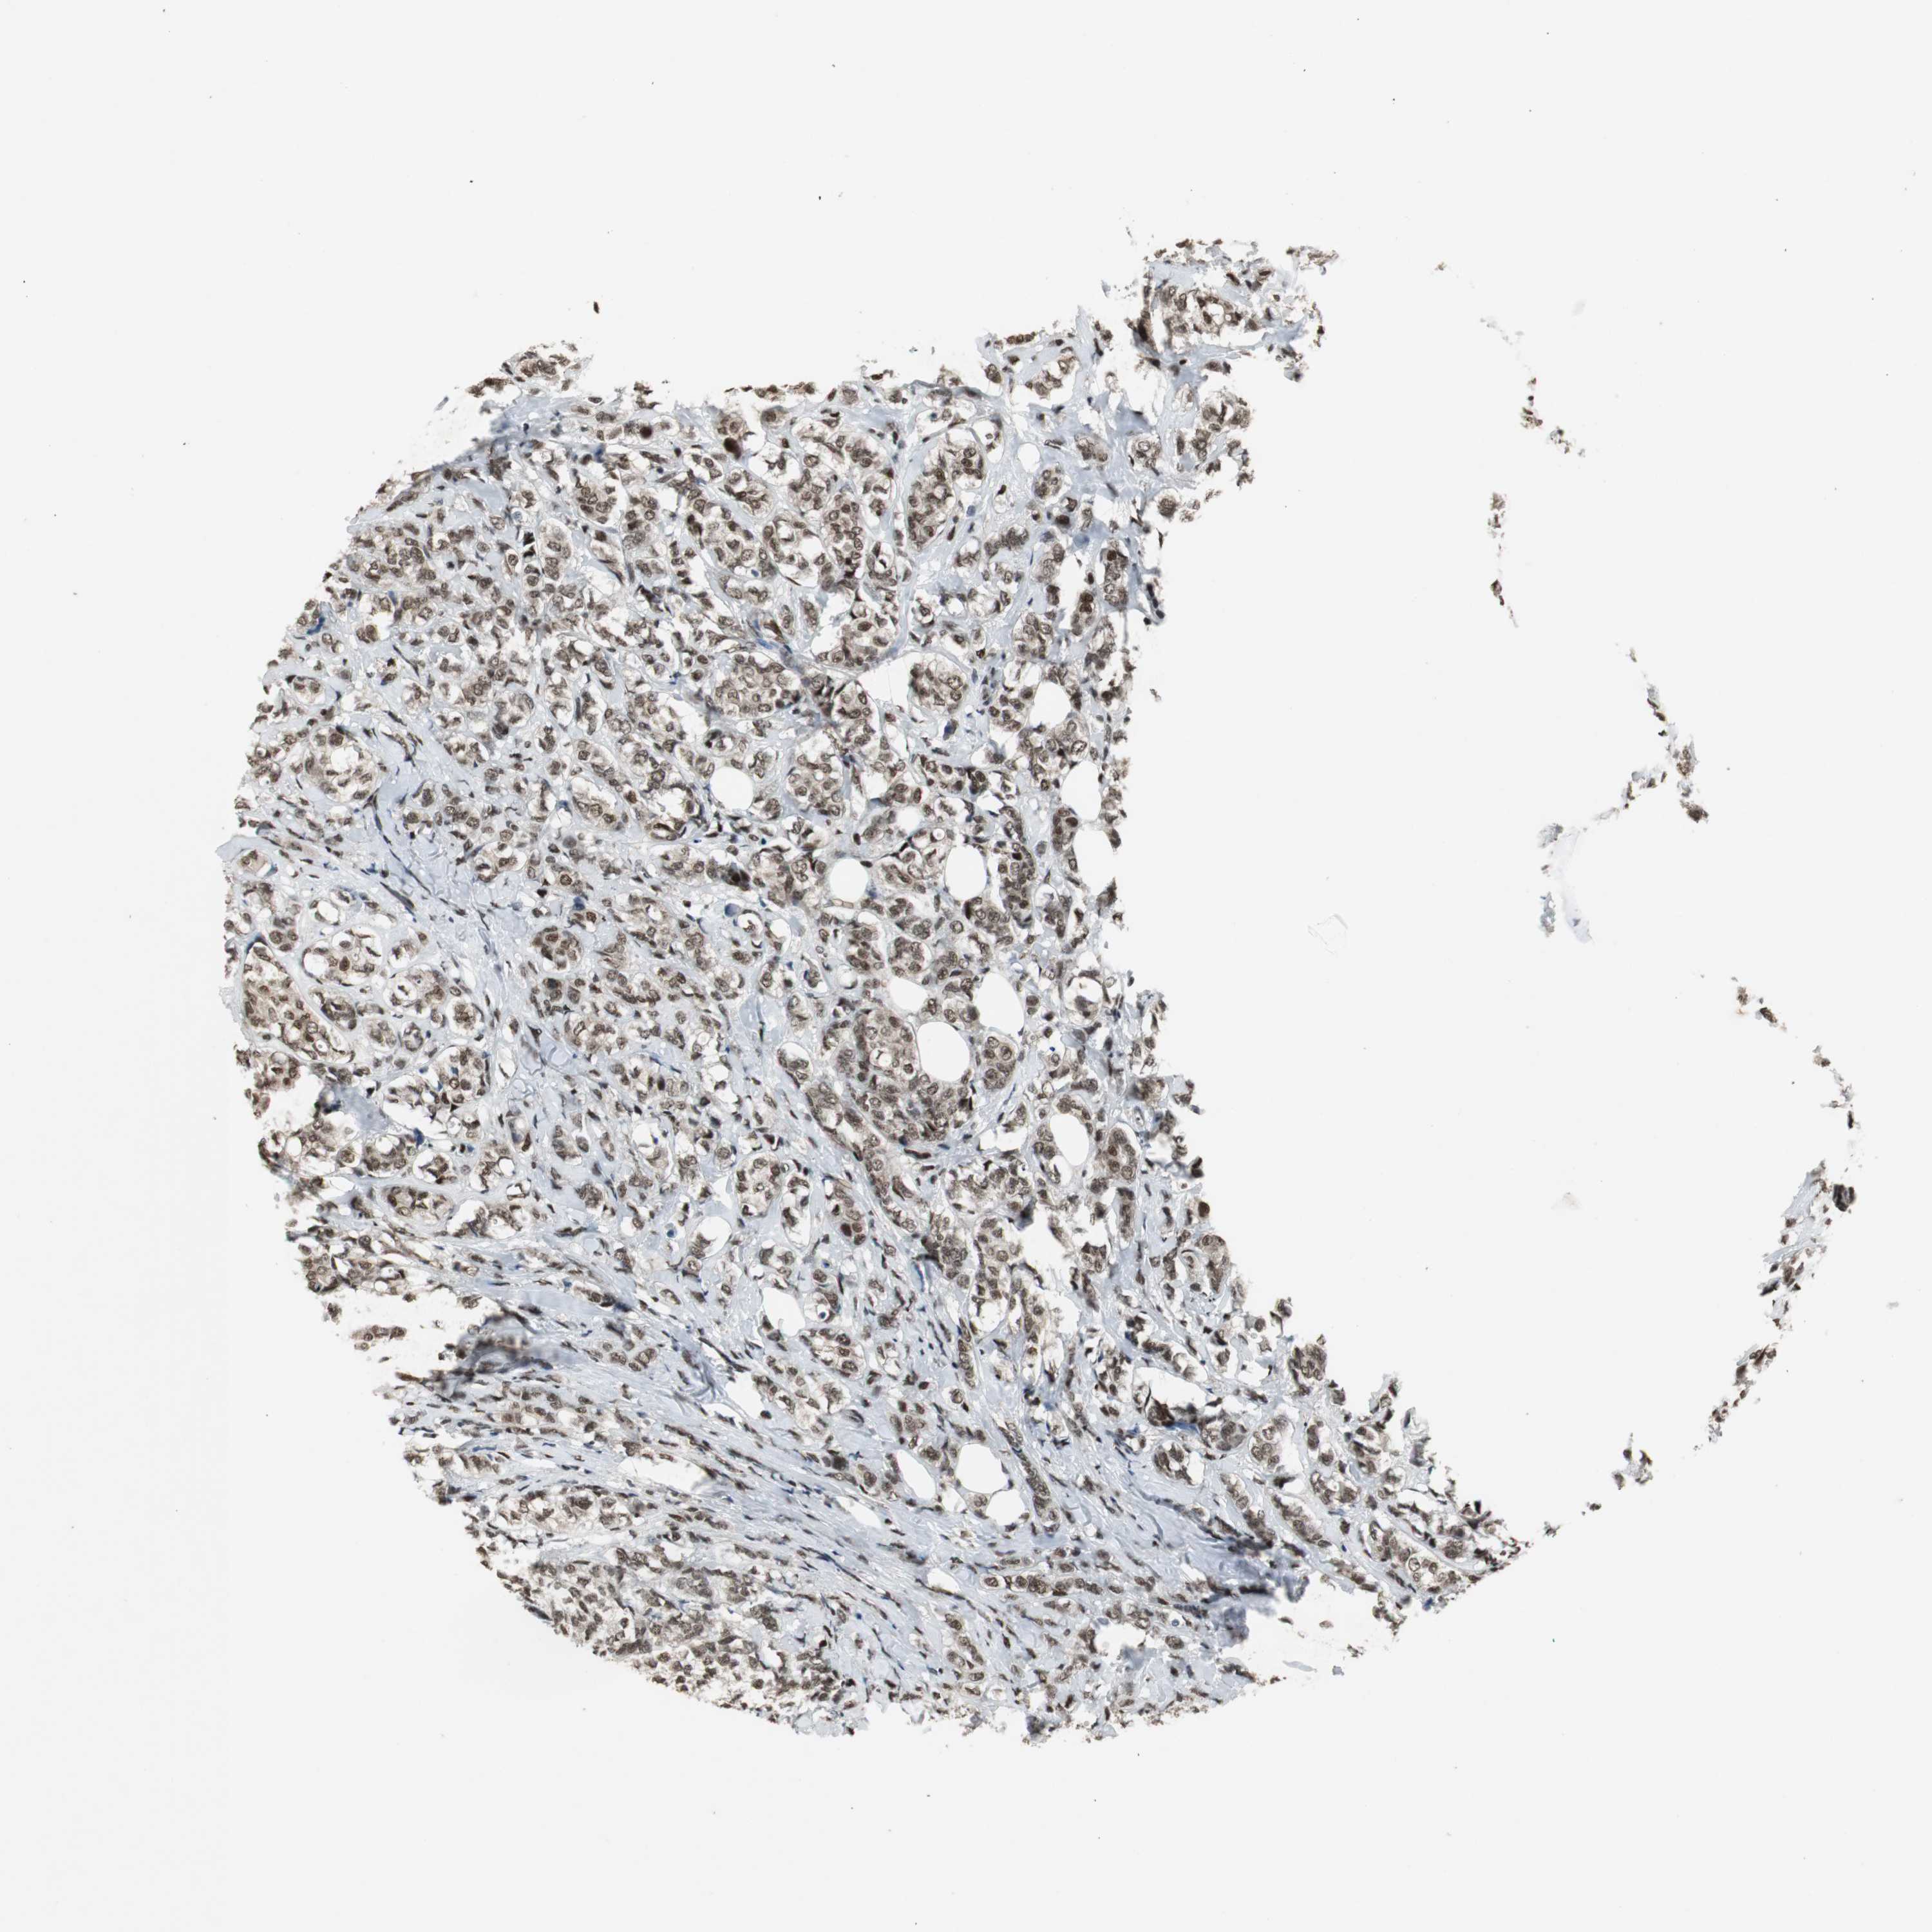

BRCA TCGA BRCA VALIDATION PROTEIN EXPRESSION

ANTIBODIES

AND

VALIDATION